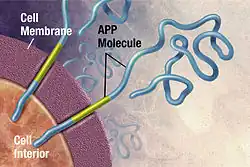

Alzheimer's disease is an incurable neurodegenerative disease which most often affects the elderly and accounts for more than half of all cases of dementia. Its exact cause remains unknown, but the disease is identified as a protein misfolding disease. Alzheimer's is associated with toxic aggregations of the amyloid beta (Aβ) peptide, caused by Aβ misfolding and clumping together with other Aβ peptides. These Aβ aggregates then grow into significantly larger senile plaques, a pathological marker of Alzheimer's disease.[49][50][51] Due to the heterogeneous nature of these aggregates, experimental methods such as X-ray crystallography and nuclear magnetic resonance (NMR) have had difficulty characterizing their structures. Moreover, atomic simulations of Aβ aggregation are highly demanding computationally due to their size and complexity.[52][53]

Preventing Aβ aggregation is a promising method to developing therapeutic drugs for Alzheimer's disease, according to Naeem and Fazili in a literature review article.[54] In 2008, Folding@home simulated the dynamics of Aβ aggregation in atomic detail over timescales of the order of tens of seconds. Prior studies were only able to simulate about 10 microseconds. Folding@home was able to simulate Aβ folding for six orders of magnitude longer than formerly possible. Researchers used the results of this study to identify a beta hairpin that was a major source of molecular interactions within the structure.[55] The study helped prepare the Pande lab for future aggregation studies and for further research to find a small peptide which may stabilize the aggregation process.[52]

In December 2008, Folding@home found several small drug candidates which appear to inhibit the toxicity of Aβ aggregates.[56] In 2010, in close cooperation with the Center for Protein Folding Machinery, these drug leads began to be tested on biological tissue.[35] In 2011, Folding@home completed simulations of several mutations of Aβ that appear to stabilize the aggregate formation, which could aid in the development of therapeutic drug therapies for the disease and greatly assist with experimental nuclear magnetic resonance spectroscopy studies of Aβ oligomers.[53][57] Later that year, Folding@home began simulations of various Aβ fragments to determine how various natural enzymes affect the structure and folding of Aβ.[58][59]